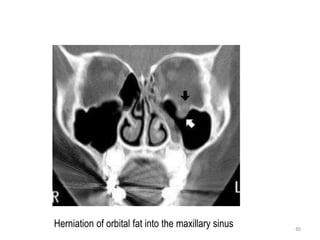

Herniation of orbital fat into the maxillary sinus

Image shows depressed fragment of the left orbital floor (arrow)

and an air-fluid level in the left maxillary sinus